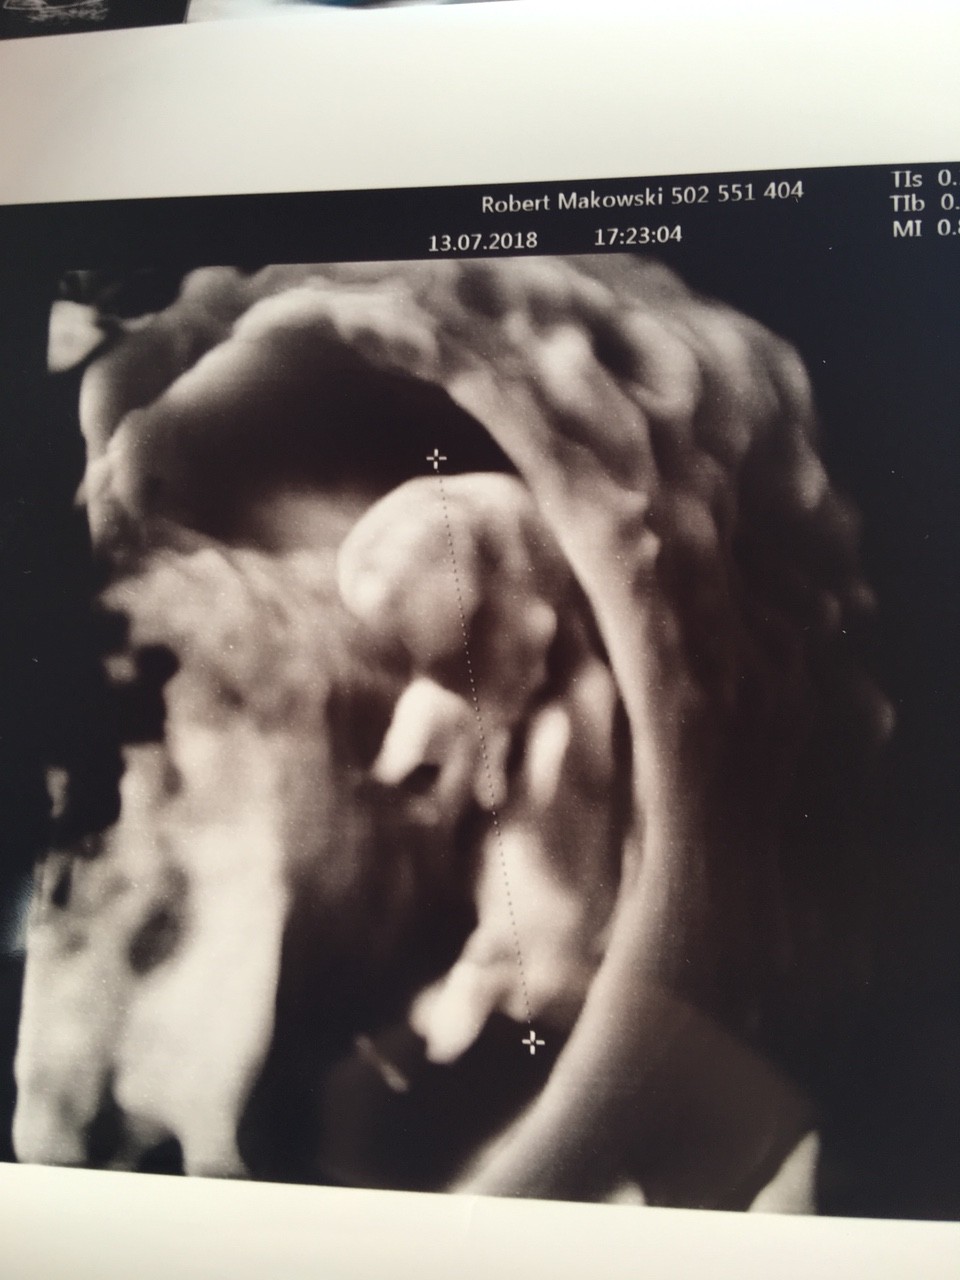

Piękności[emoji8][emoji7]I ja jestem po wizycie wszystko w porządku jak to lekarz powiedział okaz zdrowiajeśli chodzi o płeć to wstępnie dziewczynka bo nie widział żeby coś wystawało

I ja jestem po wizycie wszystko w porządku jak to lekarz powiedział okaz zdrowiajeśli chodzi o płeć to wstępnie dziewczynka bo nie widział żeby coś wystawało

Myślę że naprawdę za wcześnie żeby określić płeć mimo że lekarz ma dobre USG czy nawet w 4d. Do 16tyg kształtuje się wszystko myślę że psitka nawet teraz może wyglądać jak cycus[emoji16]Mąż ma nadzieje ze jednak coś między nogami urośnie syn tez by chciał braciszka![]()